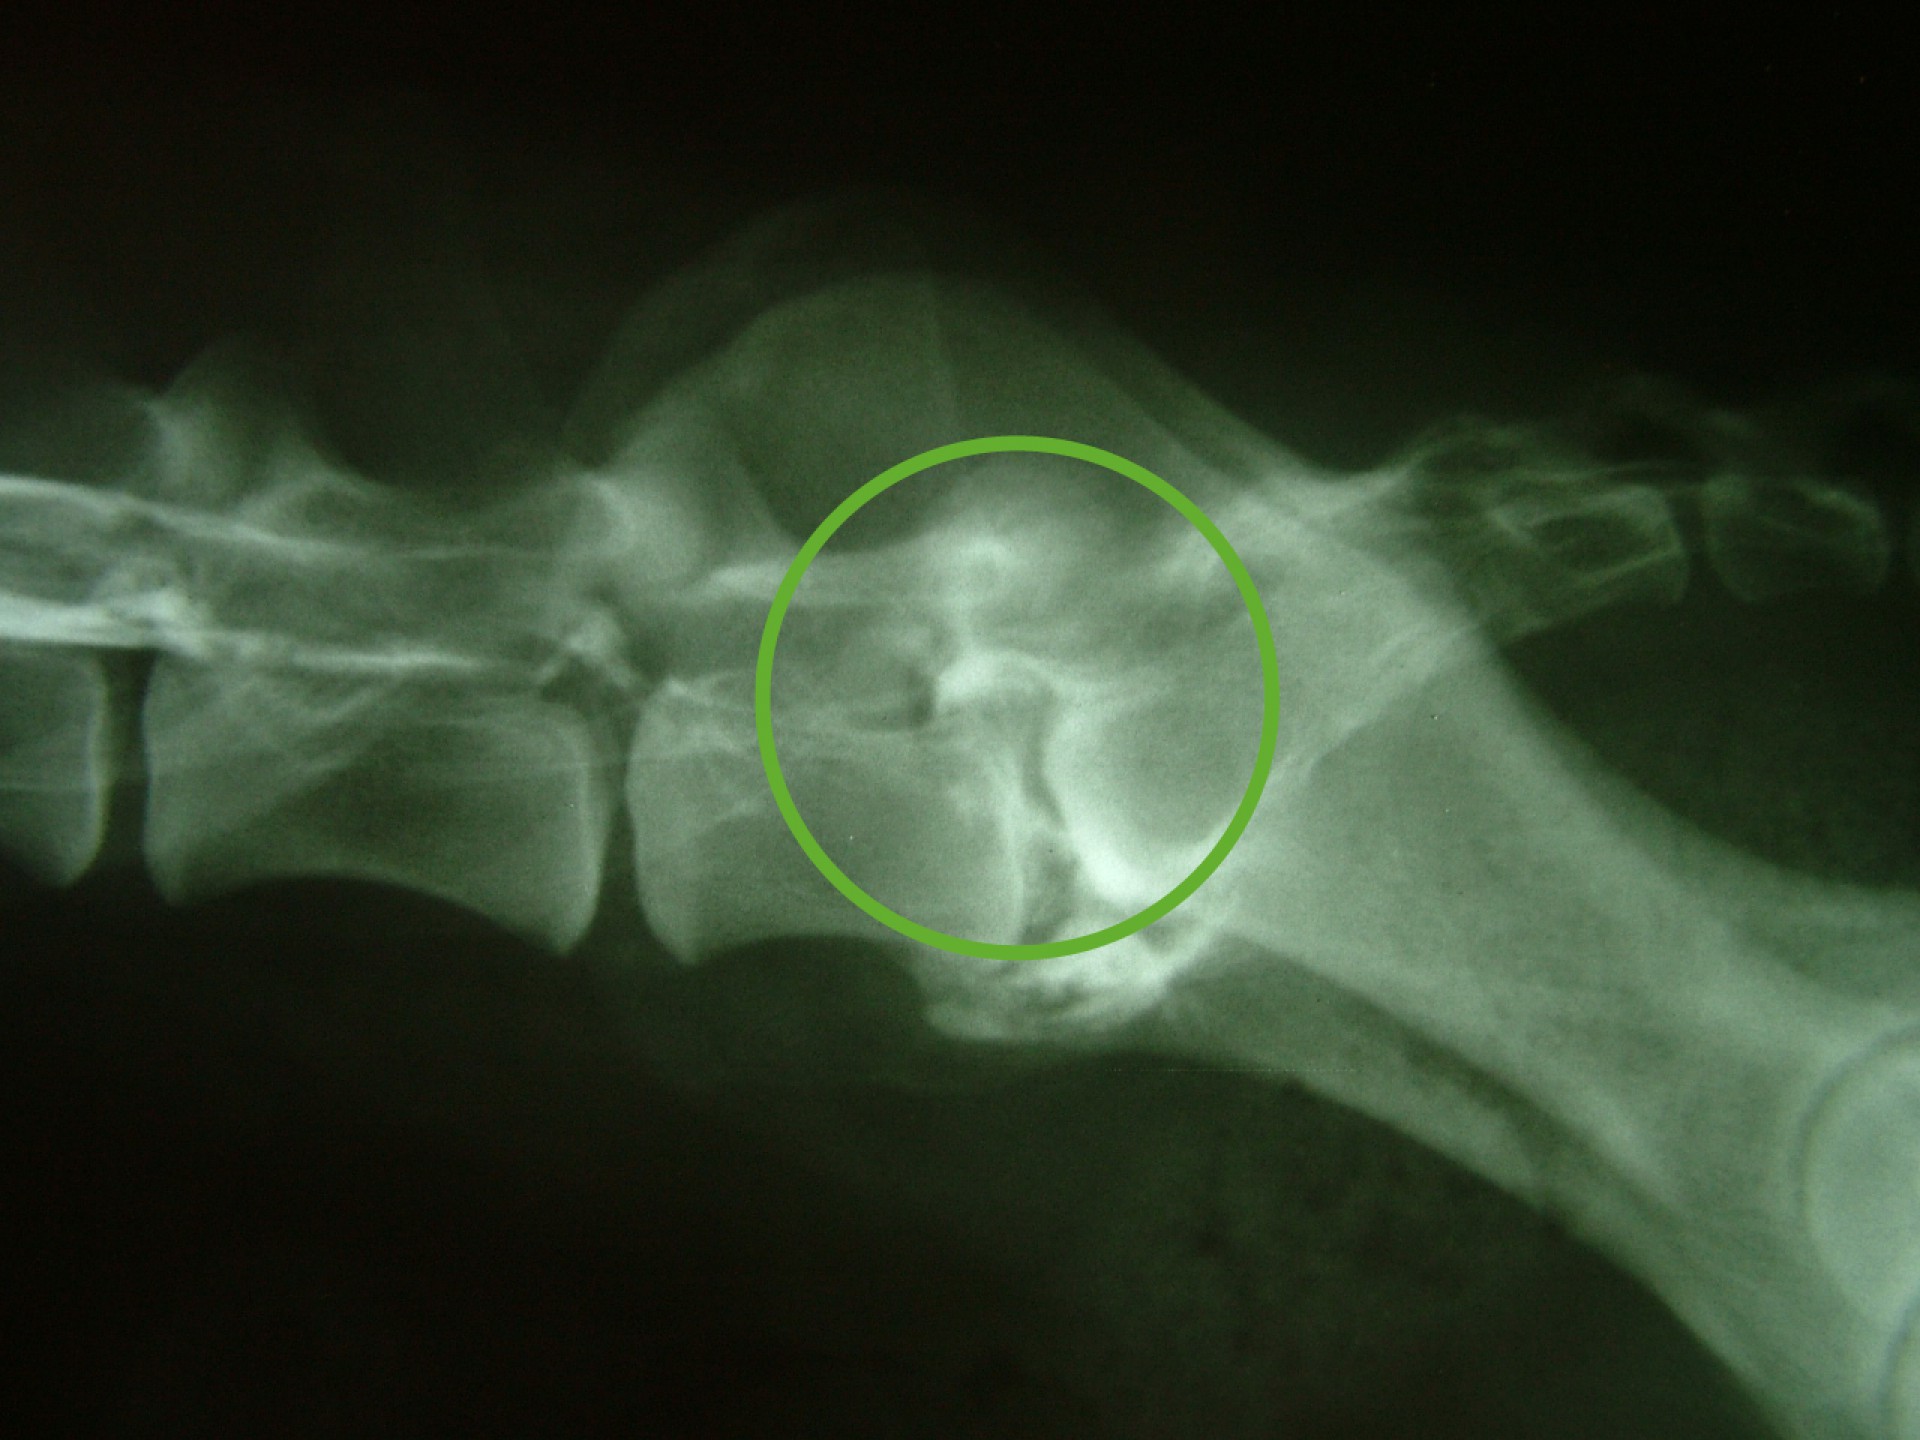

Szürke Farkas a 9 éves husky keverék kutya 4 napos csavargás után érkezett haza. Gazdája konstatálta, hogy a bal hátsó lábára sántít, így elhozta rendelőnkbe, ahol egy alapos vizsgálat után – mely során érdembeli elváltozást nem találtunk- fájdalomcsillapítókat adtunk neki és haza engedtük. Néhány nap után gazdája jelezte, hogy a kutya állapota nemhogy javulna, rosszabbodik. A kifejezett gerinctájéki fájdalmasság miatt myelographiát( gerincfestést) javasoltunk, mely során az utolsó ágyék és első keresztcsonti csigolya magasságában gerincvelő összenyomatást diagnosztizáltunk ( ld.: caudaequinacompressio). A sikeres műtétet követően néhány napon belül a fájdalom enyhült, együtt örültünk a gazdival.

Ám az öröm nem tartott sokáig. Szürke Farkas 5 nappal a műtéte után a kocsiba ugrás közben felsírt és mire a rendelőbe ért a fájdalomtól fel sem tudott állni. A kórházi felvételt követően fájdalomcsillapítók, antibiotikumok adását kezdtük meg és mivel a műtéti területen klinikai és RTG vizsgálattal sem találtunk a fájdalmat magyarázó elváltozást Kaposvárra, MRI vizsgálatra vittük. 2 nappal később meglepődve olvastuk az eredményt: a 9.-10.( Th9-Th10 ) hátcsigolyák valamint a 7 ágyéki és az 1. keresztcsonti csigolyák ( L7-S1 ) közötti porckorong gyulladásos elváltozása ( ld.: discospondylitis ) mellett a 11. és a 12. hátcsigolya magasságában ( Th 11-Th12 ) a gerincvelőt összenyomó daganatos elváltozás volt látható. Mivel a porckorongok gyulladása megmagyarázta a gerinctájéki fájdalmasságot, annak kezelése és a fájdalom további csillapítása volt az első teendőnk. Néhány nappal a fájdalom enyhülését követően a gerincvelőt összenyomó daganatot műtétileg eltávolítottuk. Ezt követően Szürke Farkas még további 60 napot töltött a kórházban. A lábadozása napról napra szépen alakult. Betegségének 90. napján hazaadtuk és a gyógyszerek további adása mellett állapotát hetente ellenőriztük.